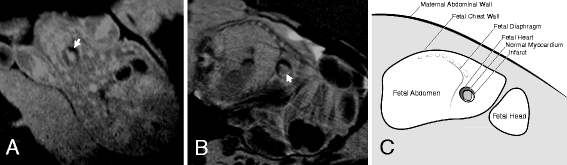

Methods: Six sheep fetuses underwent a thoracotomy and ligation of a left anterior descending (LAD) coronary artery branch; while two fetuses underwent a sham surgery. LGE CMR was performed in a subset of fetuses immediately after the surgery and three days later. Early gadolinium enhancement (EGE) CMR was also performed in a subset of fetuses on both days. Cine imaging of the heart was performed to measure ventricular function.

Results: The imaging performed immediately after LAD ligation revealed no evidence of infarct on LGE (n=3). Two of four infarcted fetuses (50%) showed hypoenhancement at the infarct site on the EGE images. Three days after the ligation, LGE images revealed a clear, hyper-enhanced infarct zone in four of the five infarcted fetuses (80%). No hyper-enhanced infarct zone was seen on the one sham fetus that underwent LGE CMR. No hypoenhancement could be seen in the EGE images in either the sham (n=1) or the infarcted fetus (n=1). No regional wall motion abnormalities were apparent in two of the five infarcted fetuses.

Conclusion: LGE CMR detected the MI three days after LAD ligation, but not immediately after. Using available methods, EGE imaging was less useful for detecting deficits in perfusion. Our study provides evidence for the ability of a non-invasive tool to monitor the progression of cardiac repair and damage in fetuses with MI. However, further investigation into the optimal timing of LGE and EGE scans and improvement of the sequences should be pursued with the aim of expanding our capacity to monitor cardiac regeneration after MI in fetal sheep.